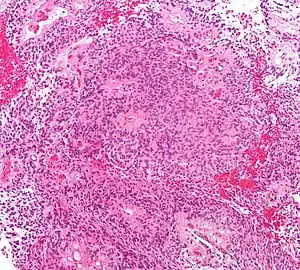

| Micrograph of an ependymoma. H&E stain. | |

Ependymomas are composed of cells with regular, round to oval nuclei. There is a variably dense fibrillary background. Tumor cells may form gland-like round or elongated structures that resemble the embryologic ependymal canal, with long, delicate processes extending into the lumen; more frequently present are perivascular pseudorosettes in which tumor cells are arranged around vessels with an intervening zone consisting of thin ependymal processes directed toward the wall of the vessel.[2]

a)Microphotographs of supratentorial ependymomas shows Grade II ependymoma b) tumor shows low MIB-1 labeling. -